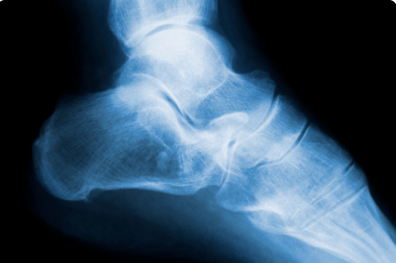

足跟骨刺x光片

足跟骨刺x光片,足跟骨刺图片

足跟骨刺图片

跟骨骨刺

踝关节x光片